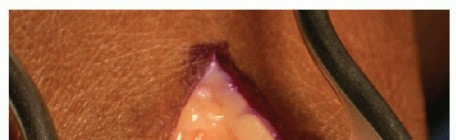

- TECH FIG 1 • Exposure of metatarsal head through dorsal approach. The extensor hallucis longus tendon is retracted laterally with the exposed metatarsal head, showing a large dorsal osteophyte and loss of articular cartilage.

Perform subperiosteal dissection to raise medial and lateral flaps off the metatarsal head and base of the proximal phalanx, exposing the joint (TECH FIG 1).3,4,19

Release the collateral ligaments and the plantar portion of the joint by releasing the plantar plate with a Freer elevator.

Remove large osteophytes and loose ossicles with a rongeur.

Resect the medial eminence from a dorsal approach with a microsagittal saw or chisel.9,14,19 -

- TECH FIG 5 • A 40-year-old man with posttraumatic arthritis of the right first MTP joint. With soft tissues well-protected, MTP joint is released, here showing release of flexor hallucis brevis tendon from base of proximal phalanx, to optimize exposure.